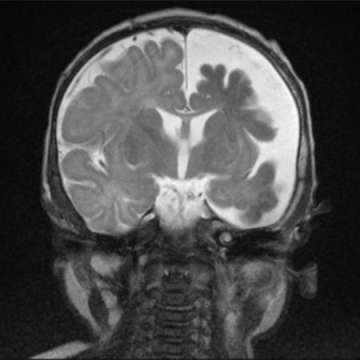

Sturge Weber Syndrome